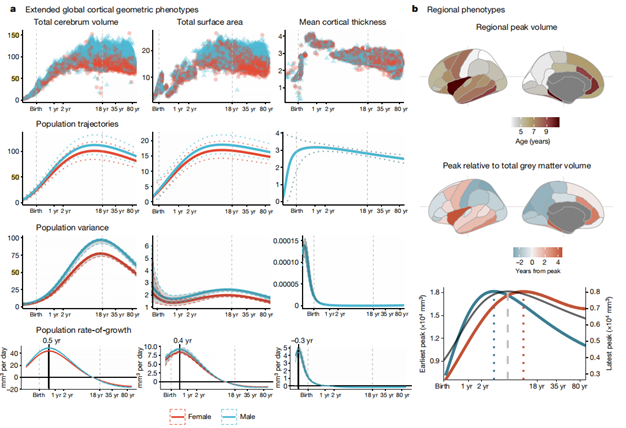

研究人员使用了GAMLSS建模方法评估了全脑范围内(平均皮质厚度和总表面积)和34个皮质区域(如图2所示)。研究发现,人脑皮层总表面积与整个生命周期中大脑总体积(TCV)的变化密切相关(图2a)。这两个指标在大约11-12岁时,都达到了峰值。相比之下,皮质厚度在1.7岁时,明显达到峰值。这与之前的研究结果一致,即皮质厚度在围产期增加,在发育后期下降。

另外,研究发现了神经发育轨迹的区域差异。与5.9岁的白质达到峰值相比,34个皮质区域的区域灰质体积的峰值的年龄变化很大,为大约2岁到10岁。初级感觉区最早达到峰值体积,达到峰值后下降较快。而额颞联合区达到峰值较晚,且达到峰值后下降较慢(图2b)。

图2:扩展的整体和区域的皮质形态表型。